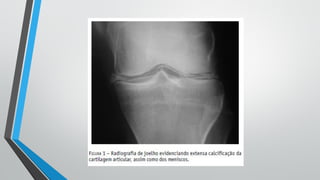

•Radiológico

• Calcificação, geralmente linear na fibrocartilagem ou cartilagem

articular

Doença por Pirofosfato– Diagnóstico •Radiológico • Calcificação, geralmente linear na fibrocartilagem ou cartilagem articular